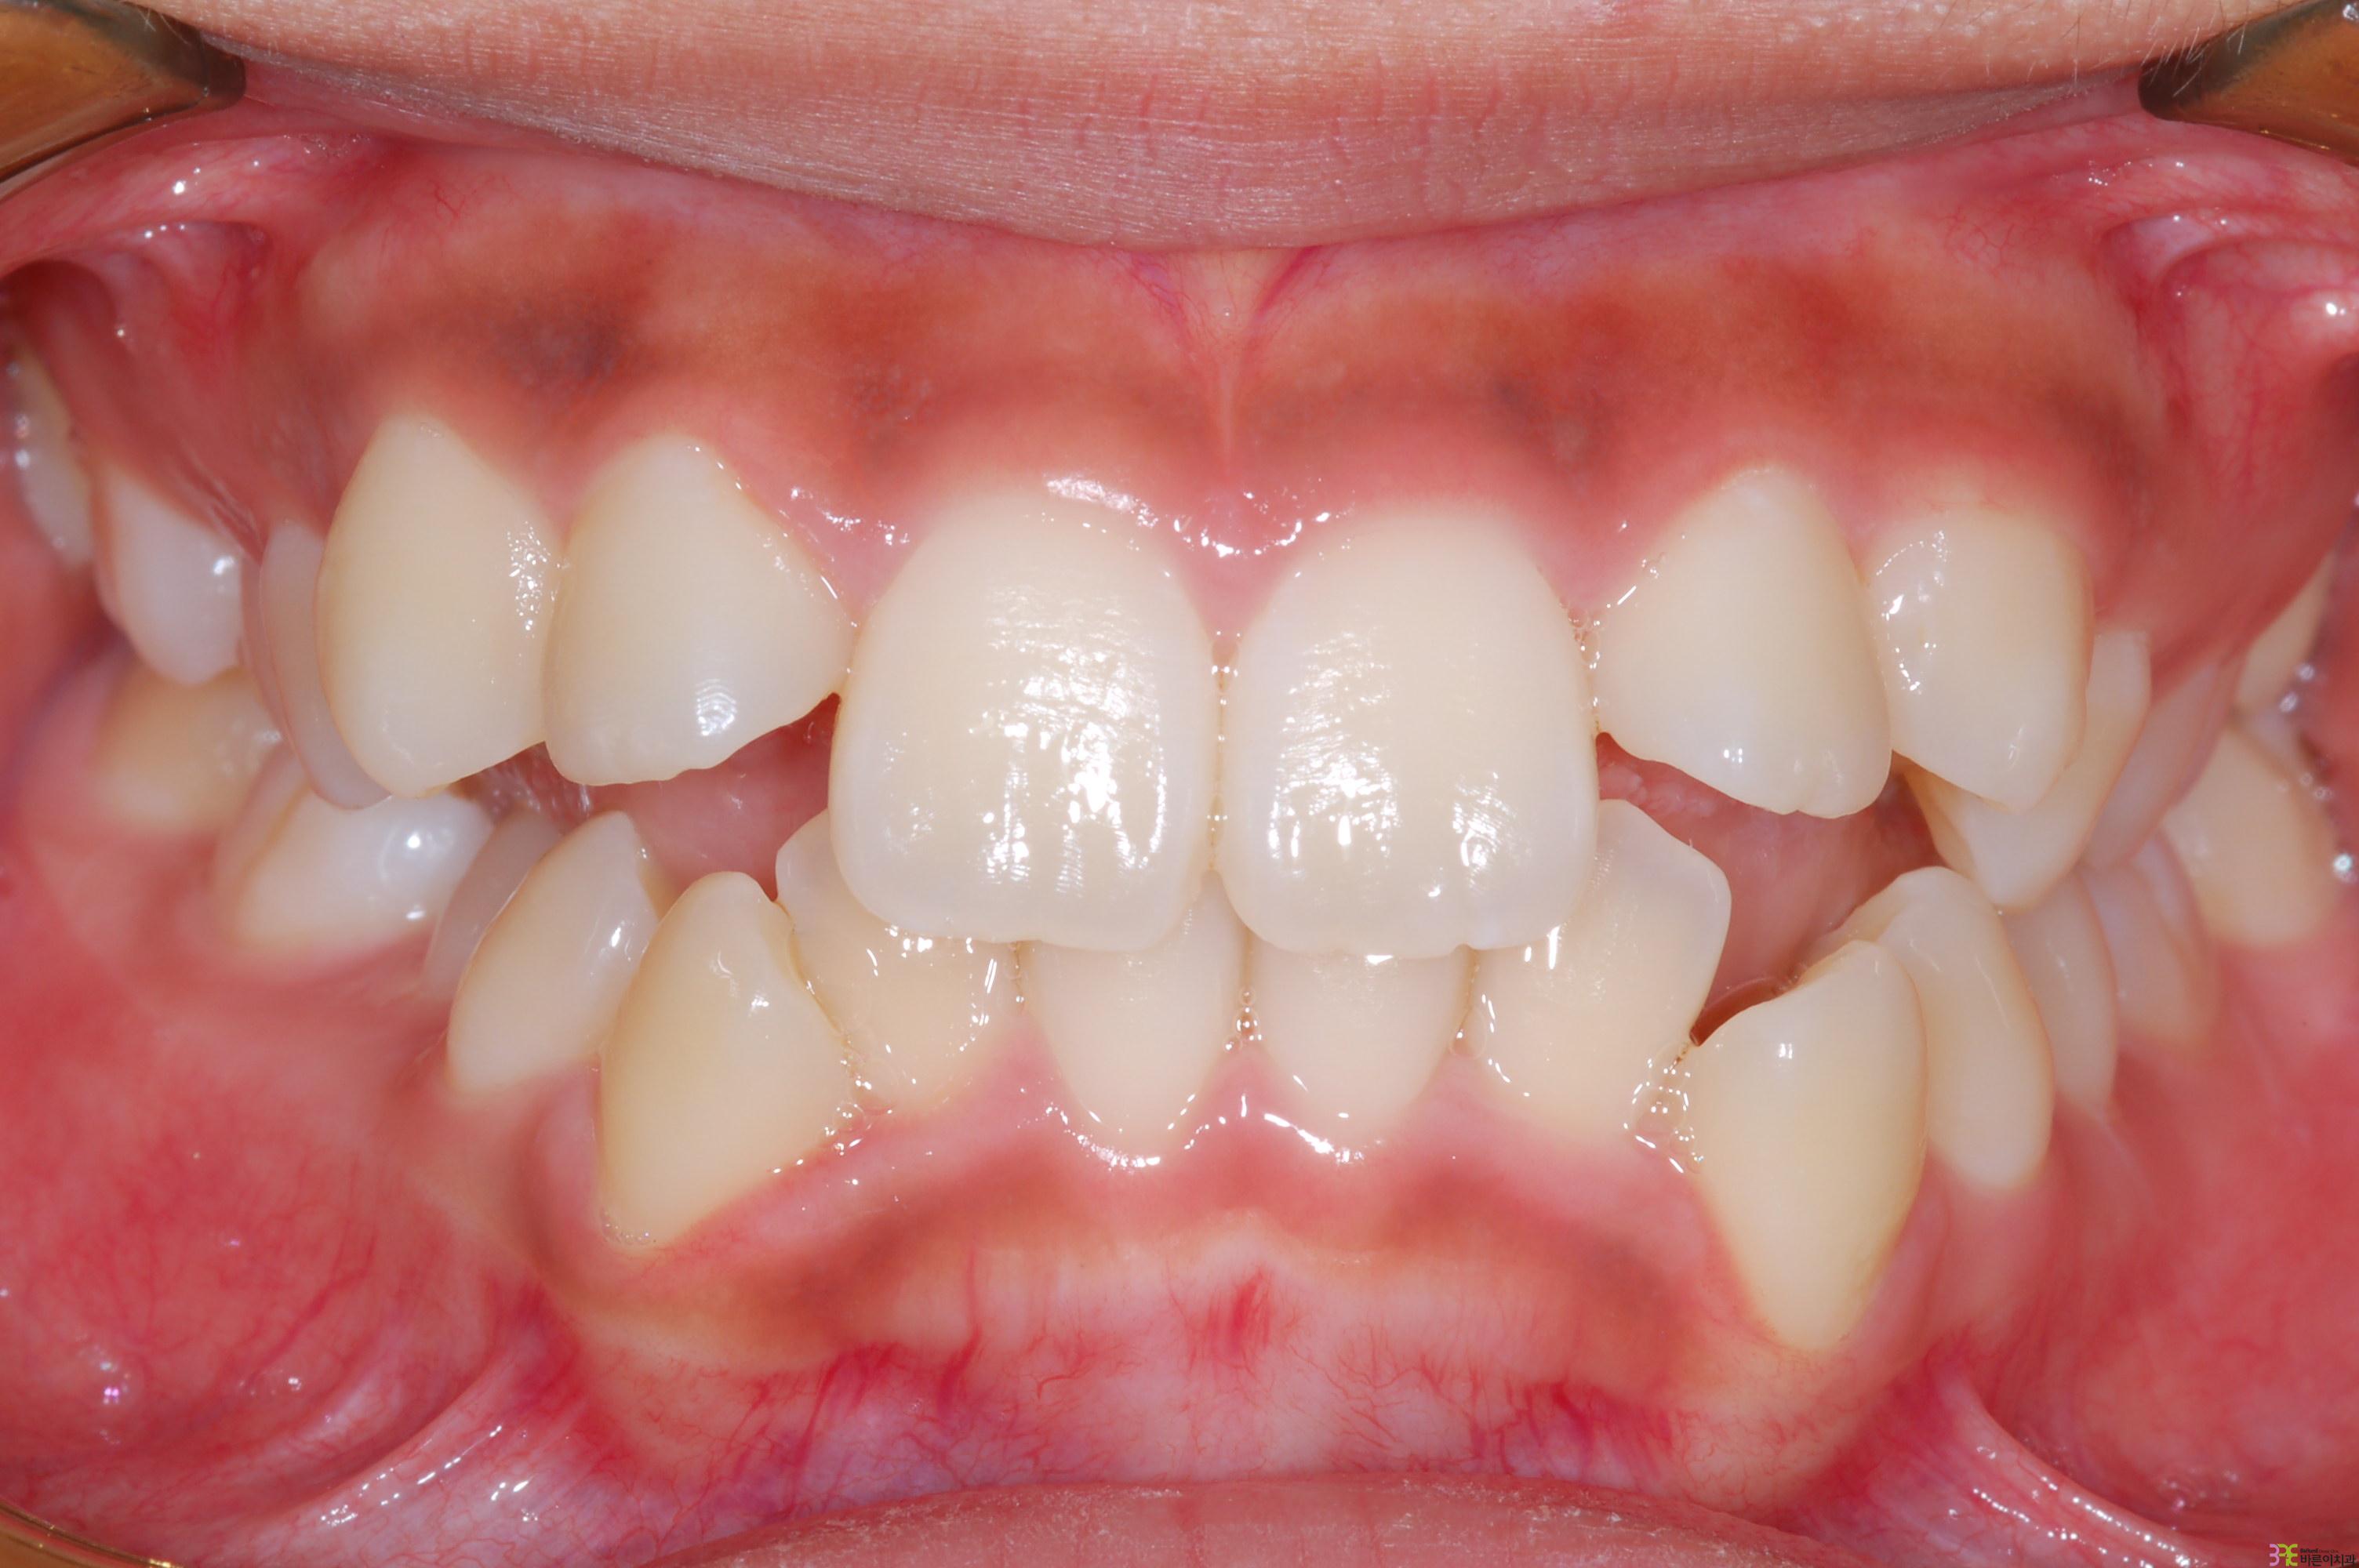

치료명

매복치 교정

치료기간

8개월

Before

After